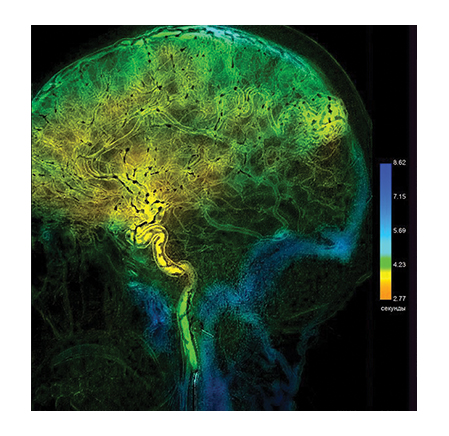

A special value of the angiography system consists in high information content of the obtained image. A unique imaging system based on a flat panel detector with spatial resolution of 50 μm, which is superior to foreign analogs regarding its specifications, ensures high diagnostic imaging quality. The examinations allow not only to obtain information about the functional state of the vessels and reveal the signs of disorders but also help determine the accurate localization and seriousness of the revealed abnormality using special calculation packages.

• Perfusion subtraction angiography for brain perfusion analysis